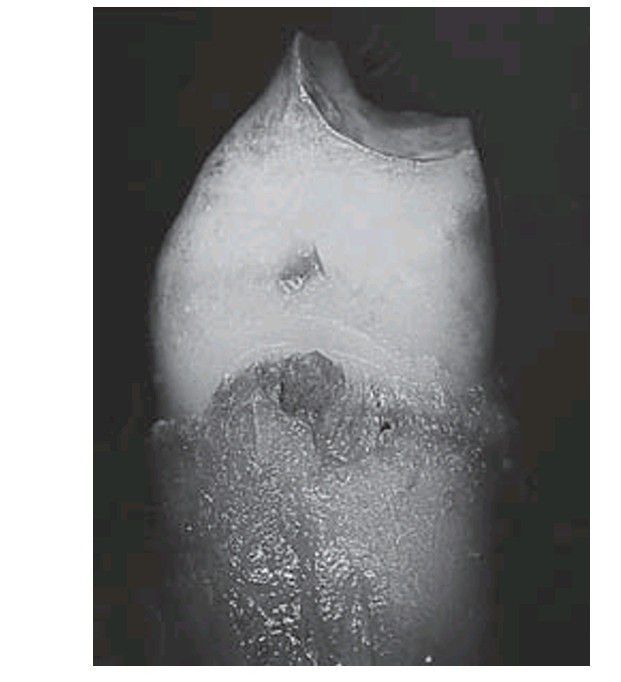

Amelogenesis imperfecta X-linked dominant hypoplastic form in a male. This premolar has a cap of enamel so thin that the shape of the tooth is virtually that of the dentine core.